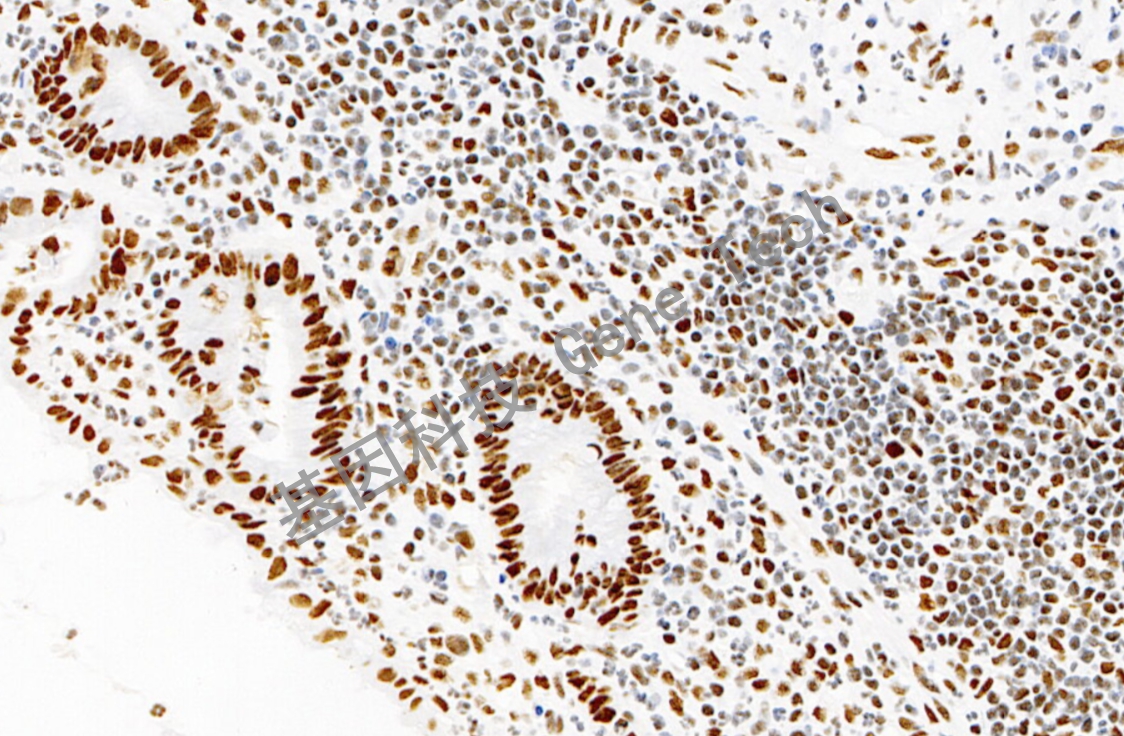

| 小腸石蠟切片,用 MSH2(GT2310)染色,細胞核陽性,DAB 顯色。 | ||

| 預處理:高pH熱修復 | 陽性部位:細胞核 | 陽性對照:結腸癌/闌尾 |